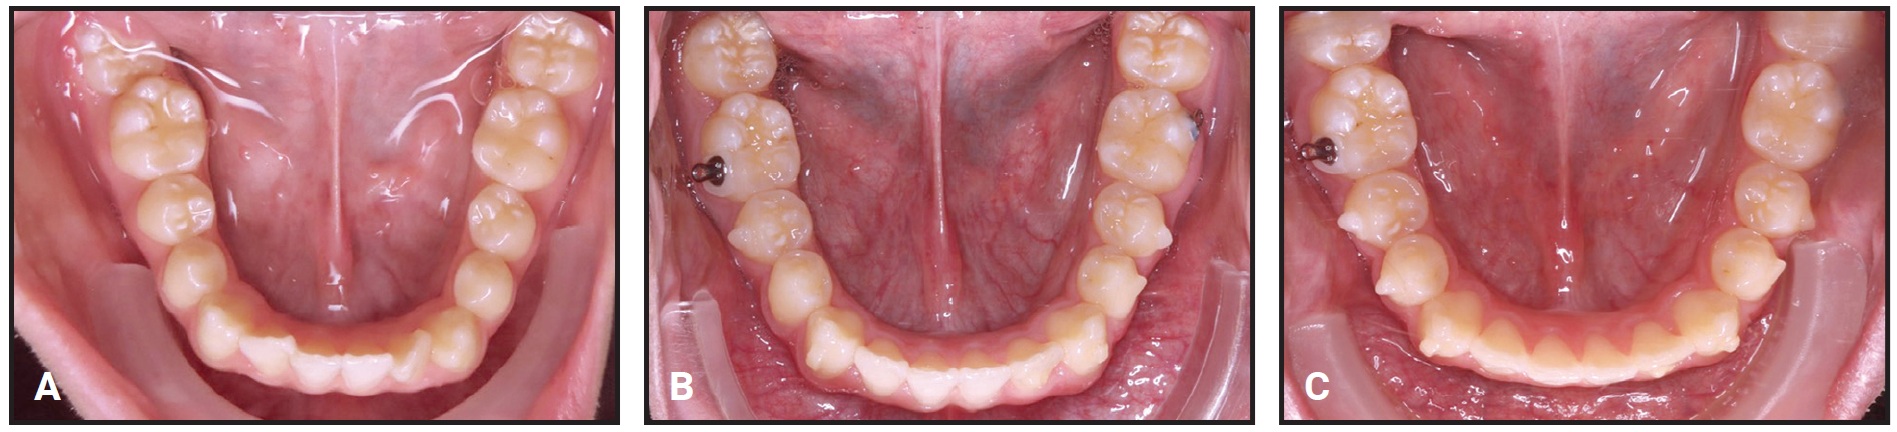

In this case, I was attempting to pull the molars for three months to no avail (Fig. 12A). A progress photograph finally made me realize that I was being stubborn in trying to close a space that wasn’t going to close, because the problem was vertical and not mesiodistal. To overcome this mistake, I repositioned the first-premolar bracket gingivally and extruded the tooth with an .016" nickel titanium archwire and 3/16" vertical intermaxillary elastics (Fig. 12B). The premolar was large enough to close the remaining space (Fig. 12C).

Fig. 12 A. Lower-molar space remaining after second-premolar extraction and three months of treatment. B. After gingival bracket repositioning, first premolar extruded using .016" nickel titanium archwire and 3/16" vertical intermaxillary elastic. C. Space finally closed, and .018" × .025" stainless steel lower archwire inserted with .010" ligature wire for stabilization.